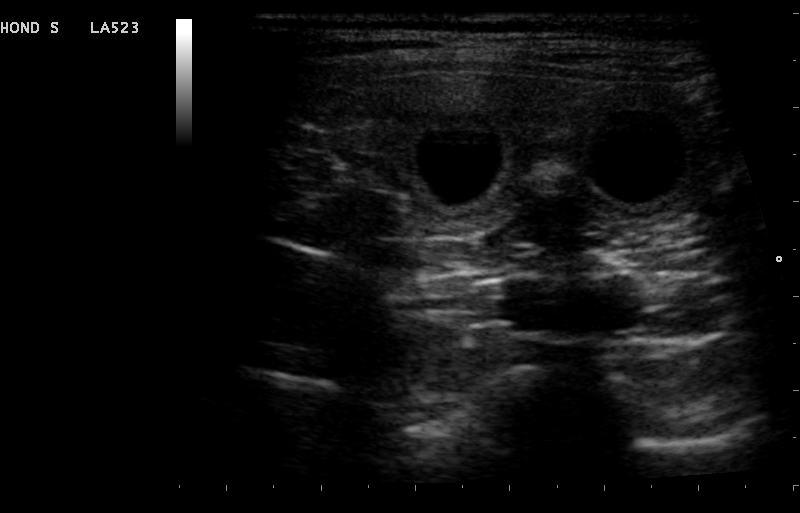

Vanaf dag 21 dagen bij de hond en 18 dagen bij de kat, is het mogelijk om te zien of een hond of kat drachtig is. Soms zijn er al eerder veranderingen waar te nemen. Het is echter betrouwbaarder om vanaf dag 28 van de dracht een echo van de baarmoeder te maken.

Er zijn dan duidelijk vruchtzakjes met foetussen zichtbaar. Vaak voeren we de echo rond dag 30 uit, omdat na die dag de kans op doodgaan en resorptie een stuk kleiner wordt.

Naast bevestigen van de dracht heeft de echo als voordeel dat het ons meer informatie geeft over de gezondheid van de pups of kittens. Er kan bekeken worden of de dracht normaal verloopt en de hartactie van de foetussen kan bekeken worden. Wanneer het moment van dekken niet bekend is, kan er een schatting gemaakt worden van de drachtduur aan de hand van het formaat van de foetussen. Hiervoor bestaan bepaalde formules, deze zijn zeker niet geheel betrouwbaar maar kunnen een richting geven. Ook kan er een schatting gemaakt worden van het aantal pups of kittens dat verwacht wordt. Het is echter belangrijk om te weten dat dit bij echo nooit met 100% zekerheid kan worden vastgesteld. Tijdens het maken van echo bewegen de foetussen, waardoor ze soms niet of juist dubbel geteld kunnen worden bij het langsgaan van de baarmoederhoorns. Ook is het zo dat hoe verder we in de dracht zitten, des te onbetrouwbaarder wordt het. Dit komt omdat de pups en kittens steeds groter worden, waardoor je meerdere keren hetzelfde pup of kitten kunt tellen.